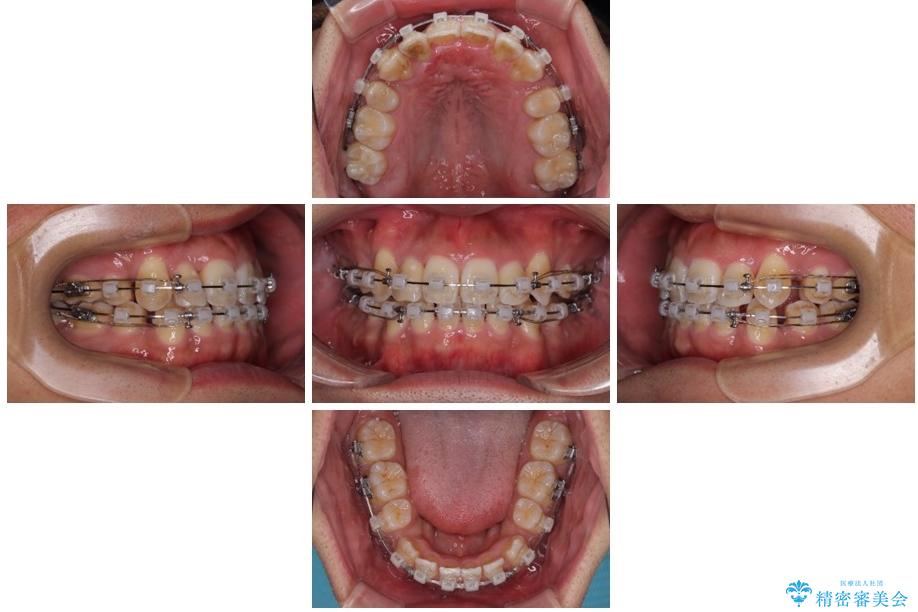

治療後

八重歯はきれいに整い、前歯もバランスよく収まり、横顔のラインも自然に改善されました。

治療後、患者様は「思い切り笑えるようになった」と大変喜んでくださいました。